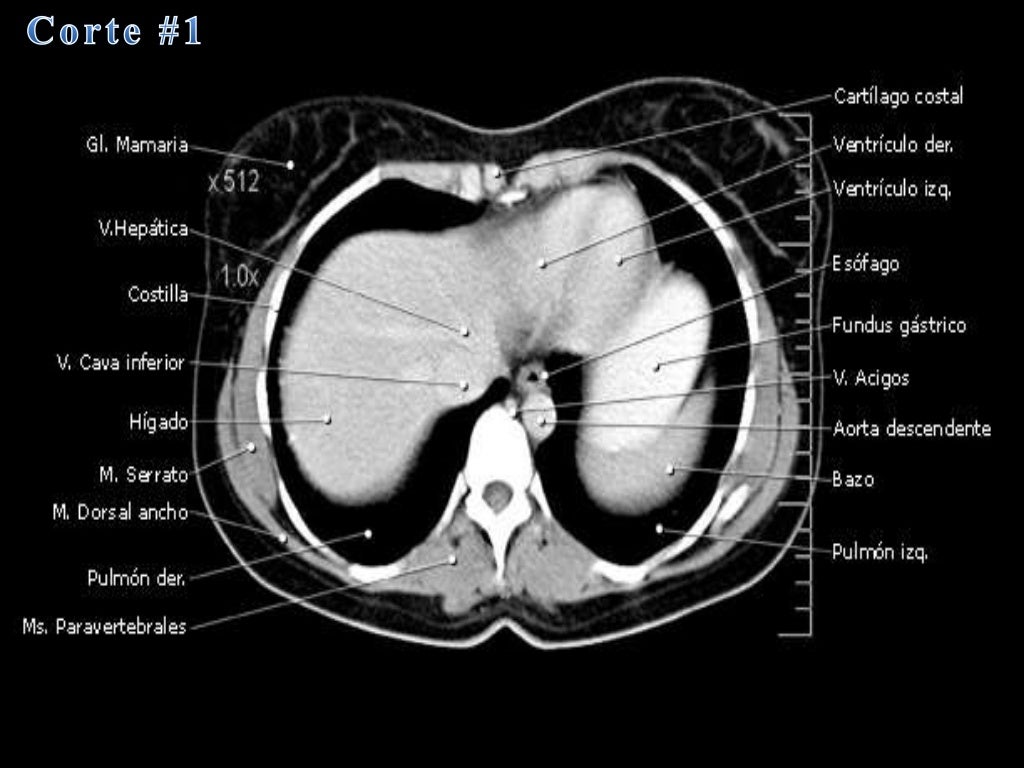

La tomografía computarizada, más comunmente conocida como exploración por tc o tac, es un examen médico de diagnóstico por imágenes.

que es una tomografia abdominal La tomografía computarizada, más comunmente conocida como exploración por tc o tac, es un examen médico de diagnóstico por imágenes. La angiotomografía computarizada del corazón es una forma útil de detectar arterias coronarias obstruidas. Una tomografía computada abdominal utiliza una máquina especial de rayos x para tomar imágenes del hígado, bazo, riñones, vejiga, estómago, intestinos, páncreas y glándulas. Una tomografía de abdomen es un estudio de imagen que ayuda a detectar problemas de salud en el área del abdomen. Una tomografía computada abdominal utiliza una máquina especial de rayos x para tomar imágenes del hígado, bazo, riñones,. La tomografía computarizada, tc, es un procedimiento con imágenes que usa equipo especial de rayos x para crear imágenes detalladas, o exploraciones, de regiones. Al igual que los rayos x. La angiotomografía computarizada podría costar menos que una.